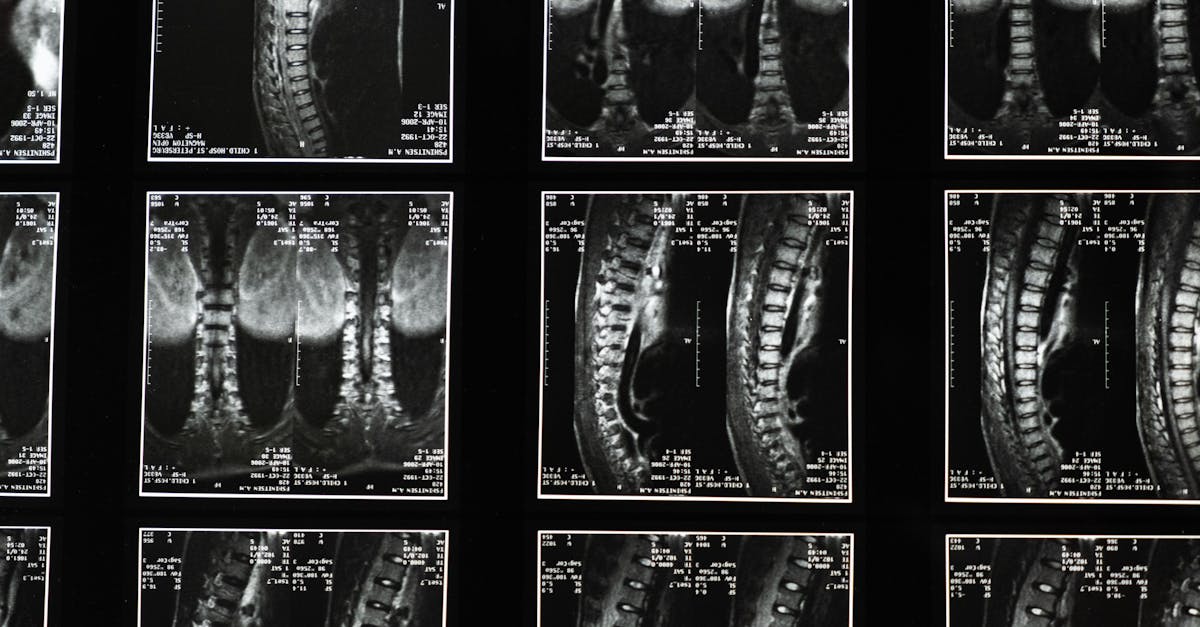

y encuentre una ubicación cerca de usted aquí: https://pulsealign.com/our-locations/ Alivio transformador con la tecnología de descompresión espinal de TAGMED TAGMED ofrece una avanzada terapia de descompresión espinal, una solución no quirúrgica diseñada específicamente para tratar problemas discales de moderados a graves, como hernias discales, protrusiones discales y estenosis espinal. Al reducir suavemente la presión sobre los discos y nervios afectados, esta técnica especializada ayuda a mejorar la movilidad, aliviar el dolor y favorece el proceso natural de curación del cuerpo. Si se ha estancado con otras terapias, descubra cómo el enfoque de descompresión basado en la evidencia de TAGMED puede ayudarle a retomar una vida activa y cómoda.¿Ha probado tratamientos convencionales y aún sufre de dolor de espalda persistente debido a una afección discal grave?

TAGMED La descompresión neurovertebral aplica una fuerza de tracción controlada y progresiva a la columna vertebral. Este método aumenta eficazmente el espacio entre las vértebras, reduciendo así la presión sobre los discos intervertebrales y las raíces nerviosas. El proceso promueve una mejor circulación de líquidos en la zona afectada, lo que ayuda a reducir la inflamación y aliviar el dolor. Esta solución fiable y no invasiva es especialmente beneficiosa para personas con problemas crónicos de espalda, ya que activa un mecanismo de regeneración tisular que alivia las molestias. Beneficios específicos Este enfoque no invasivo alivia eficazmente el dolor crónico y los síntomas asociados a afecciones como la hernia discal y la estenosis espinal. Al reducir la presión sobre las estructuras nerviosas y optimizar la circulación de líquidos alrededor de los discos, los pacientes experimentan una recuperación más rápida y una mejor calidad de vida. Quienes padecen afecciones como ciática y protrusión discal pueden beneficiarse especialmente, experimentando mejoras que les permiten retomar sus actividades cotidianas. Comparación con otros tratamientos Al comparar la tecnología de descompresión neurovertebral de TAGMED con otros tratamientos comunes, como analgésicos, inyecciones de corticosteroides o incluso cirugía, queda claro por qué esta terapia destaca. A diferencia de las intervenciones invasivas que conllevan riesgos inherentes, el enfoque de TAGMED minimiza los efectos secundarios relacionados con la medicación y ofrece una vía de recuperación potencialmente más rápida. Este método natural apoya los mecanismos de autorregulación del cuerpo, lo que lo convierte en una opción atractiva para quienes buscan alternativas más seguras y basadas en la evidencia. Casos prácticos o testimonios Ejemplos reales ejemplifican los beneficios transformadores de la descompresión neurovertebral de TAGMED. Terapia. Numerosos pacientes han reportado un alivio duradero del dolor y una reanudación más rápida de sus actividades diarias después del tratamiento. Un paciente compartió: «Después de unas pocas sesiones, me sentí completamente diferente. Por fin podía moverme sin dolor y realizar actividades que creía perdidas». Estos testimonios de primera mano resaltan los resultados tangibles y las ventajas prácticas de este enfoque terapéutico para quienes lidian con dolor crónico y otros síntomas relacionados.Experimente hoy mismo los beneficios transformadores de la Terapia de Descompresión Espinal de TAGMED.